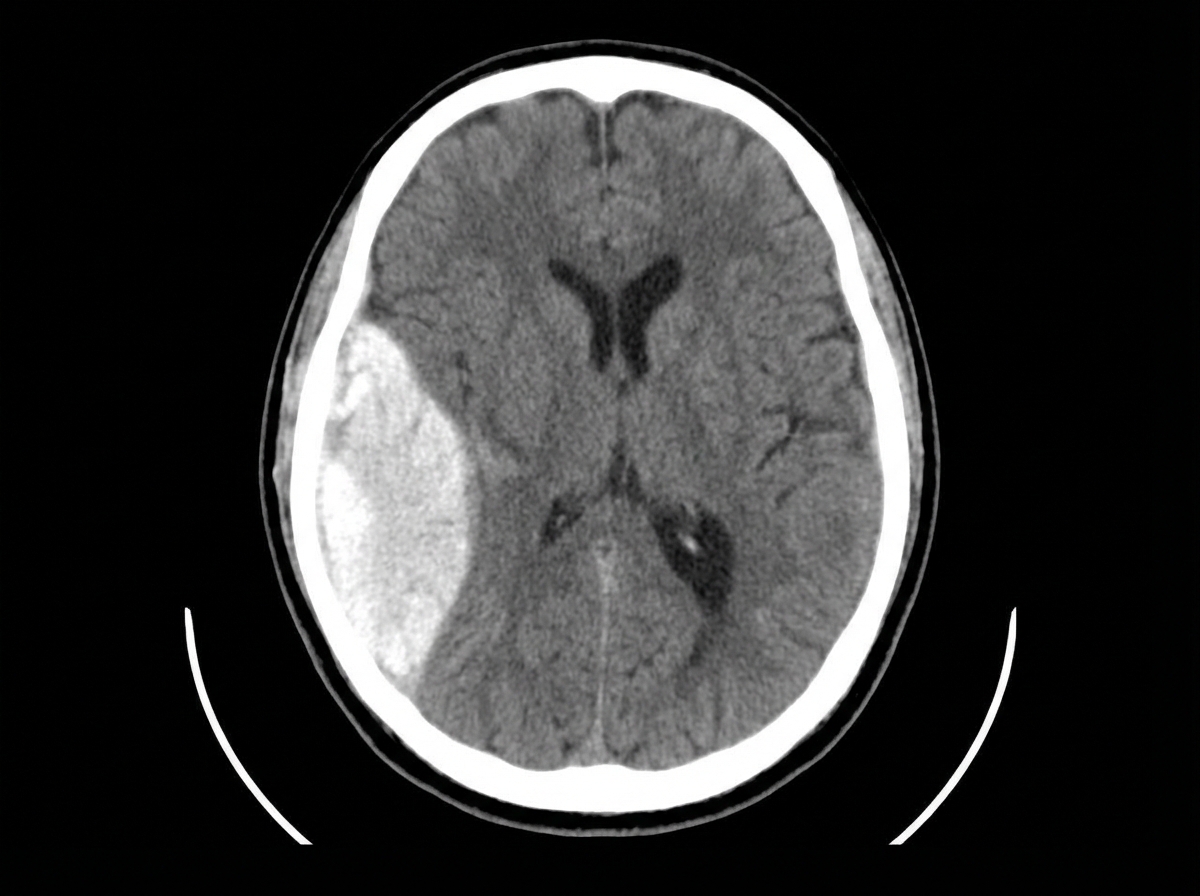

A 30-year-old patient with a head injury presented to the emergency department. NCCT findings are provided. All of the following are true about this condition except:

Explanation: ***Full recovery is rare even after treatment*** - This statement is **incorrect** - full recovery is actually **common** with prompt surgical treatment of epidural hematoma. - Early recognition and **immediate surgical evacuation** leads to excellent prognosis in most cases, making this the exception among the given statements. *Lucid interval is positive* - **Classic feature** of epidural hematoma where patient initially loses consciousness, then appears normal before deteriorating. - Occurs due to **progressive hematoma expansion** causing delayed compression of brain structures. *Immediate surgical evacuation should be done* - **Emergency craniotomy** and hematoma evacuation is the standard treatment for epidural hematoma. - Delay in surgical intervention can lead to **brain herniation** and death due to increasing intracranial pressure. *Arterial bleeding* - Epidural hematoma typically results from **middle meningeal artery** rupture following temporal bone fracture. - **High-pressure arterial bleeding** causes rapid hematoma formation, unlike venous subdural hematomas.